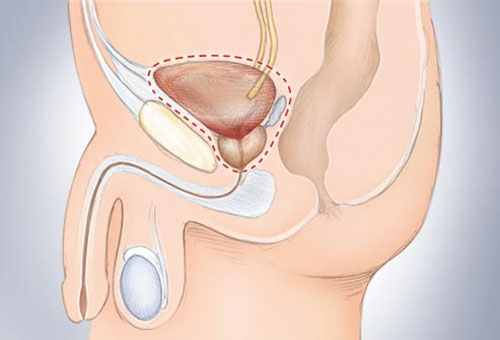

Nếu ung thư đã xâm lấn sâu hơn trong bàng quang, các bác sĩ phẫu thuật sẽ có nhiều khả năng thực hiện cắt bỏ một phần của bàng quang hoặc cắt bỏ toàn bộ bàng quang. Đối với nam giới, tuyến tiền liệt và niệu đạo cũng có thể được phẫu thuật cắt bỏ. Đối với phụ nữ, có thể phải cắt bỏ tử cung, ống dẫn trứng, buồng trứng và một phần của âm đạo.

Đối với nam giới, tuyến tiền liệt và niệu đạo cũng có thể được phẫu thuật cắt bỏ.